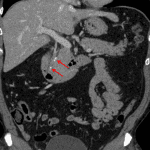

- Multiple radiopaque common bile duct calculi including a 3 mm calculus near the Sphincter of Oddi and a more proximal calculus measuring 5 x 11 mm

- Hyperenhancement of the extrahepatic bile duct walls and gallbladder wall with mild adjacent fat stranding

- No gallbladder or biliary duct dilation

- Ascending cholangitis

Choledocholithiasis with findings concerning for ascending cholangitis. No biliary duct dilation.